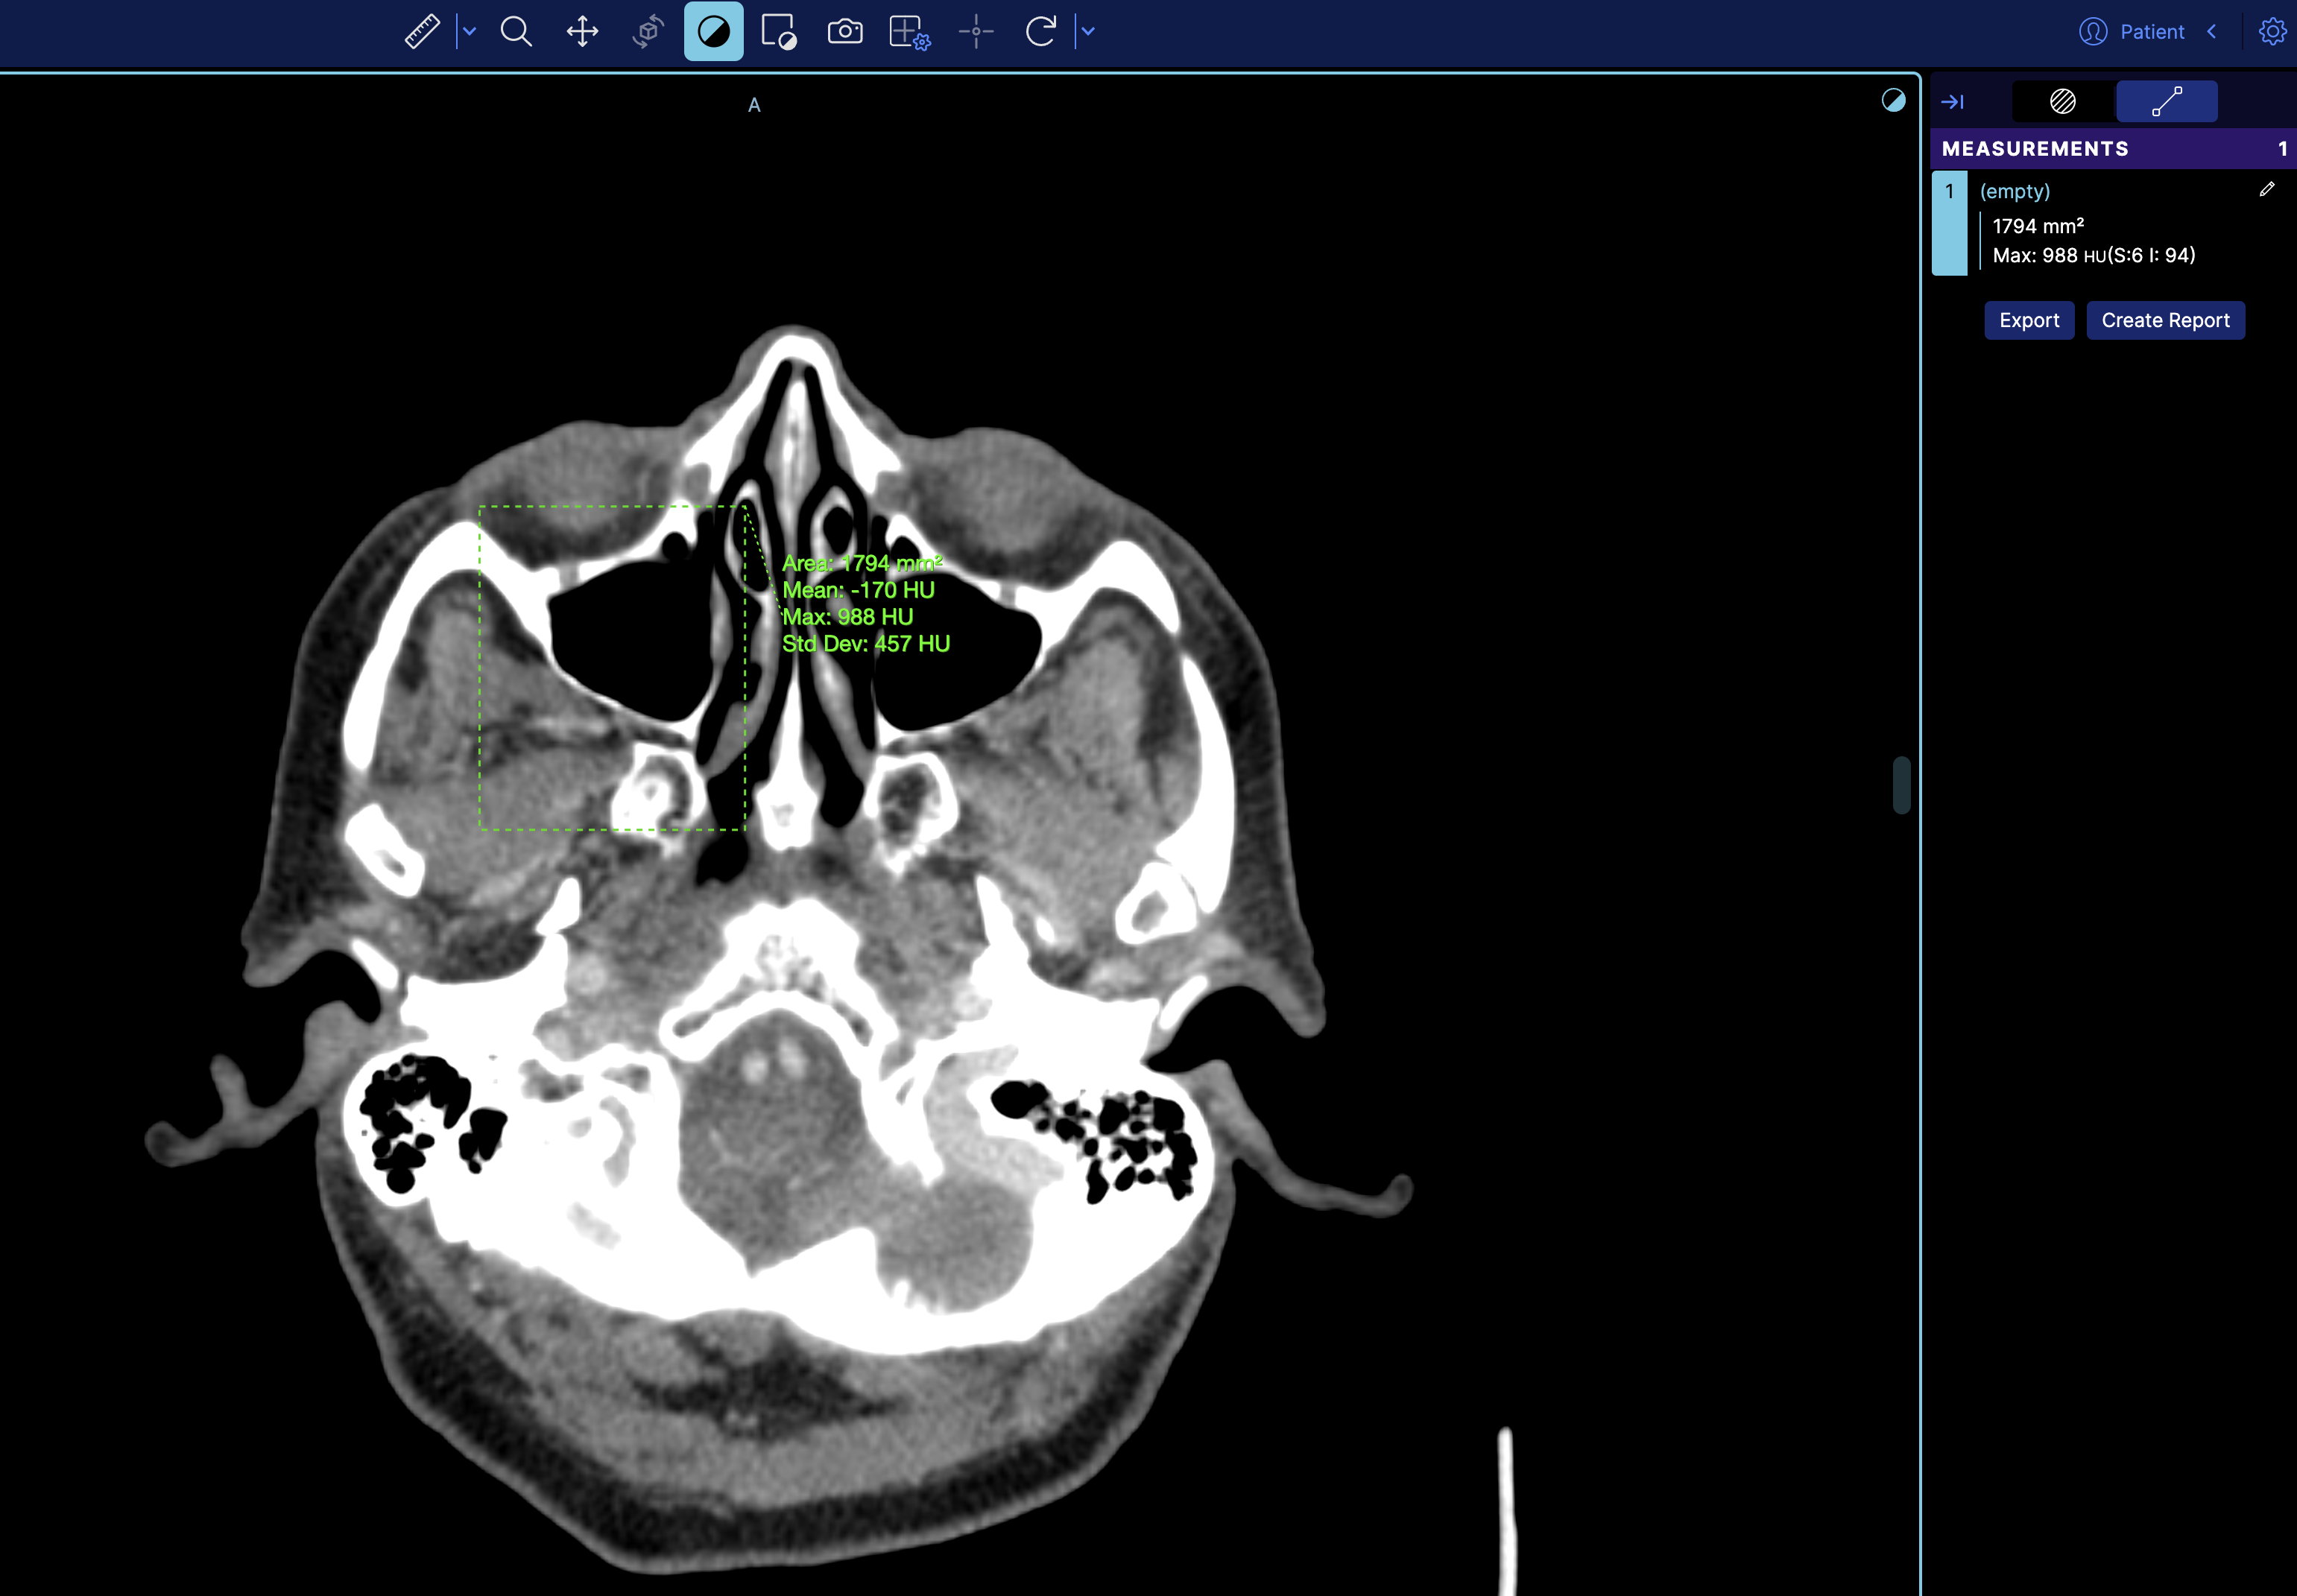

So if we look at the terminal and get the measurement service we can see there is one measurement

However, this is the mapped cornerstone measurement inside OHIF, and it has additional information such as geReport and source, which are internal details of OHIF Viewers that you don't need to worry about.

If you refresh the viewer, you'll see the measurement loaded on the image.

which then it will look like